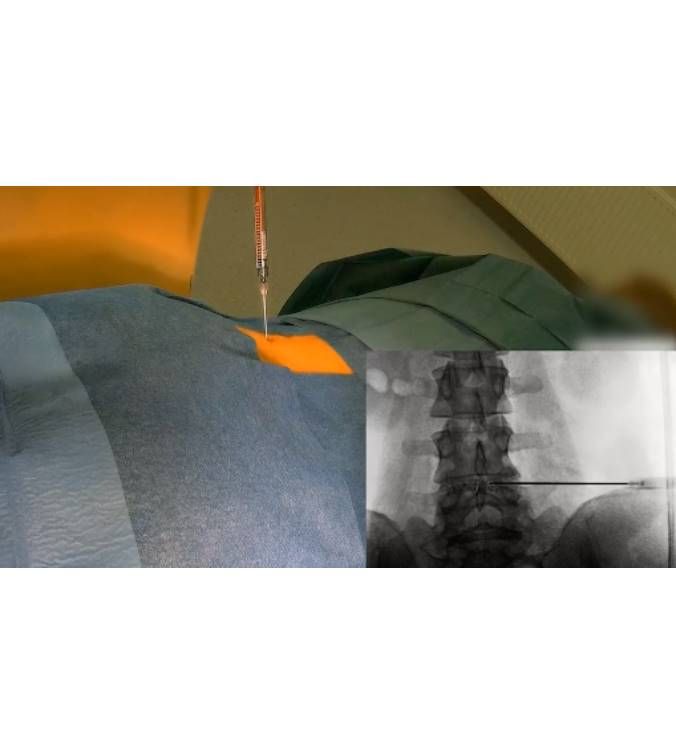

Η δισκοπλαστική αποτελεί μια καινοτόμο τεχνική ελάχιστης επεμβατικότητας. Εφαρμόζεται σε παθήσεις των μεσοσπονδυλίων δίσκων οι οποίοι δημιουργούν λειτουργικά ενοχλήματα σε κάποιο επίπεδο της σπονδυλικής στήλης (συχνότερα προσβαλλόμενη η οσφυική μοίρα της σπονδυλικής στήλης).

Η τεχνική δεν απαιτεί τομές καθώς με χρήση βελόνης και ακτινοσκοπική καθοδήγηση προσεγγίζουμε το σημείο της βλάβης και τοποθετούμε το ενδοδοσκικό υλικό. (Discogel)

Το υλικό αυτό δημιουργεί δομικές αλλαγές στον φθαρμένο δίσκο επιτυγχάνοντας ενυδάτωση, συρρίκνωση και αλλαγή στο κολλαγό του.

Προοδευτικά ο πηκτοειδής πυρήνας του δίσκου γίνεται ισχυρότερος και καταφέρνει να αντισταθεί στις πιέσεις που δέχεται. Αυτό οδηγεί σε εξάλειψη του πόνου και στην βελτίωση της κλινικής σημειολογίας του ασθενούς.